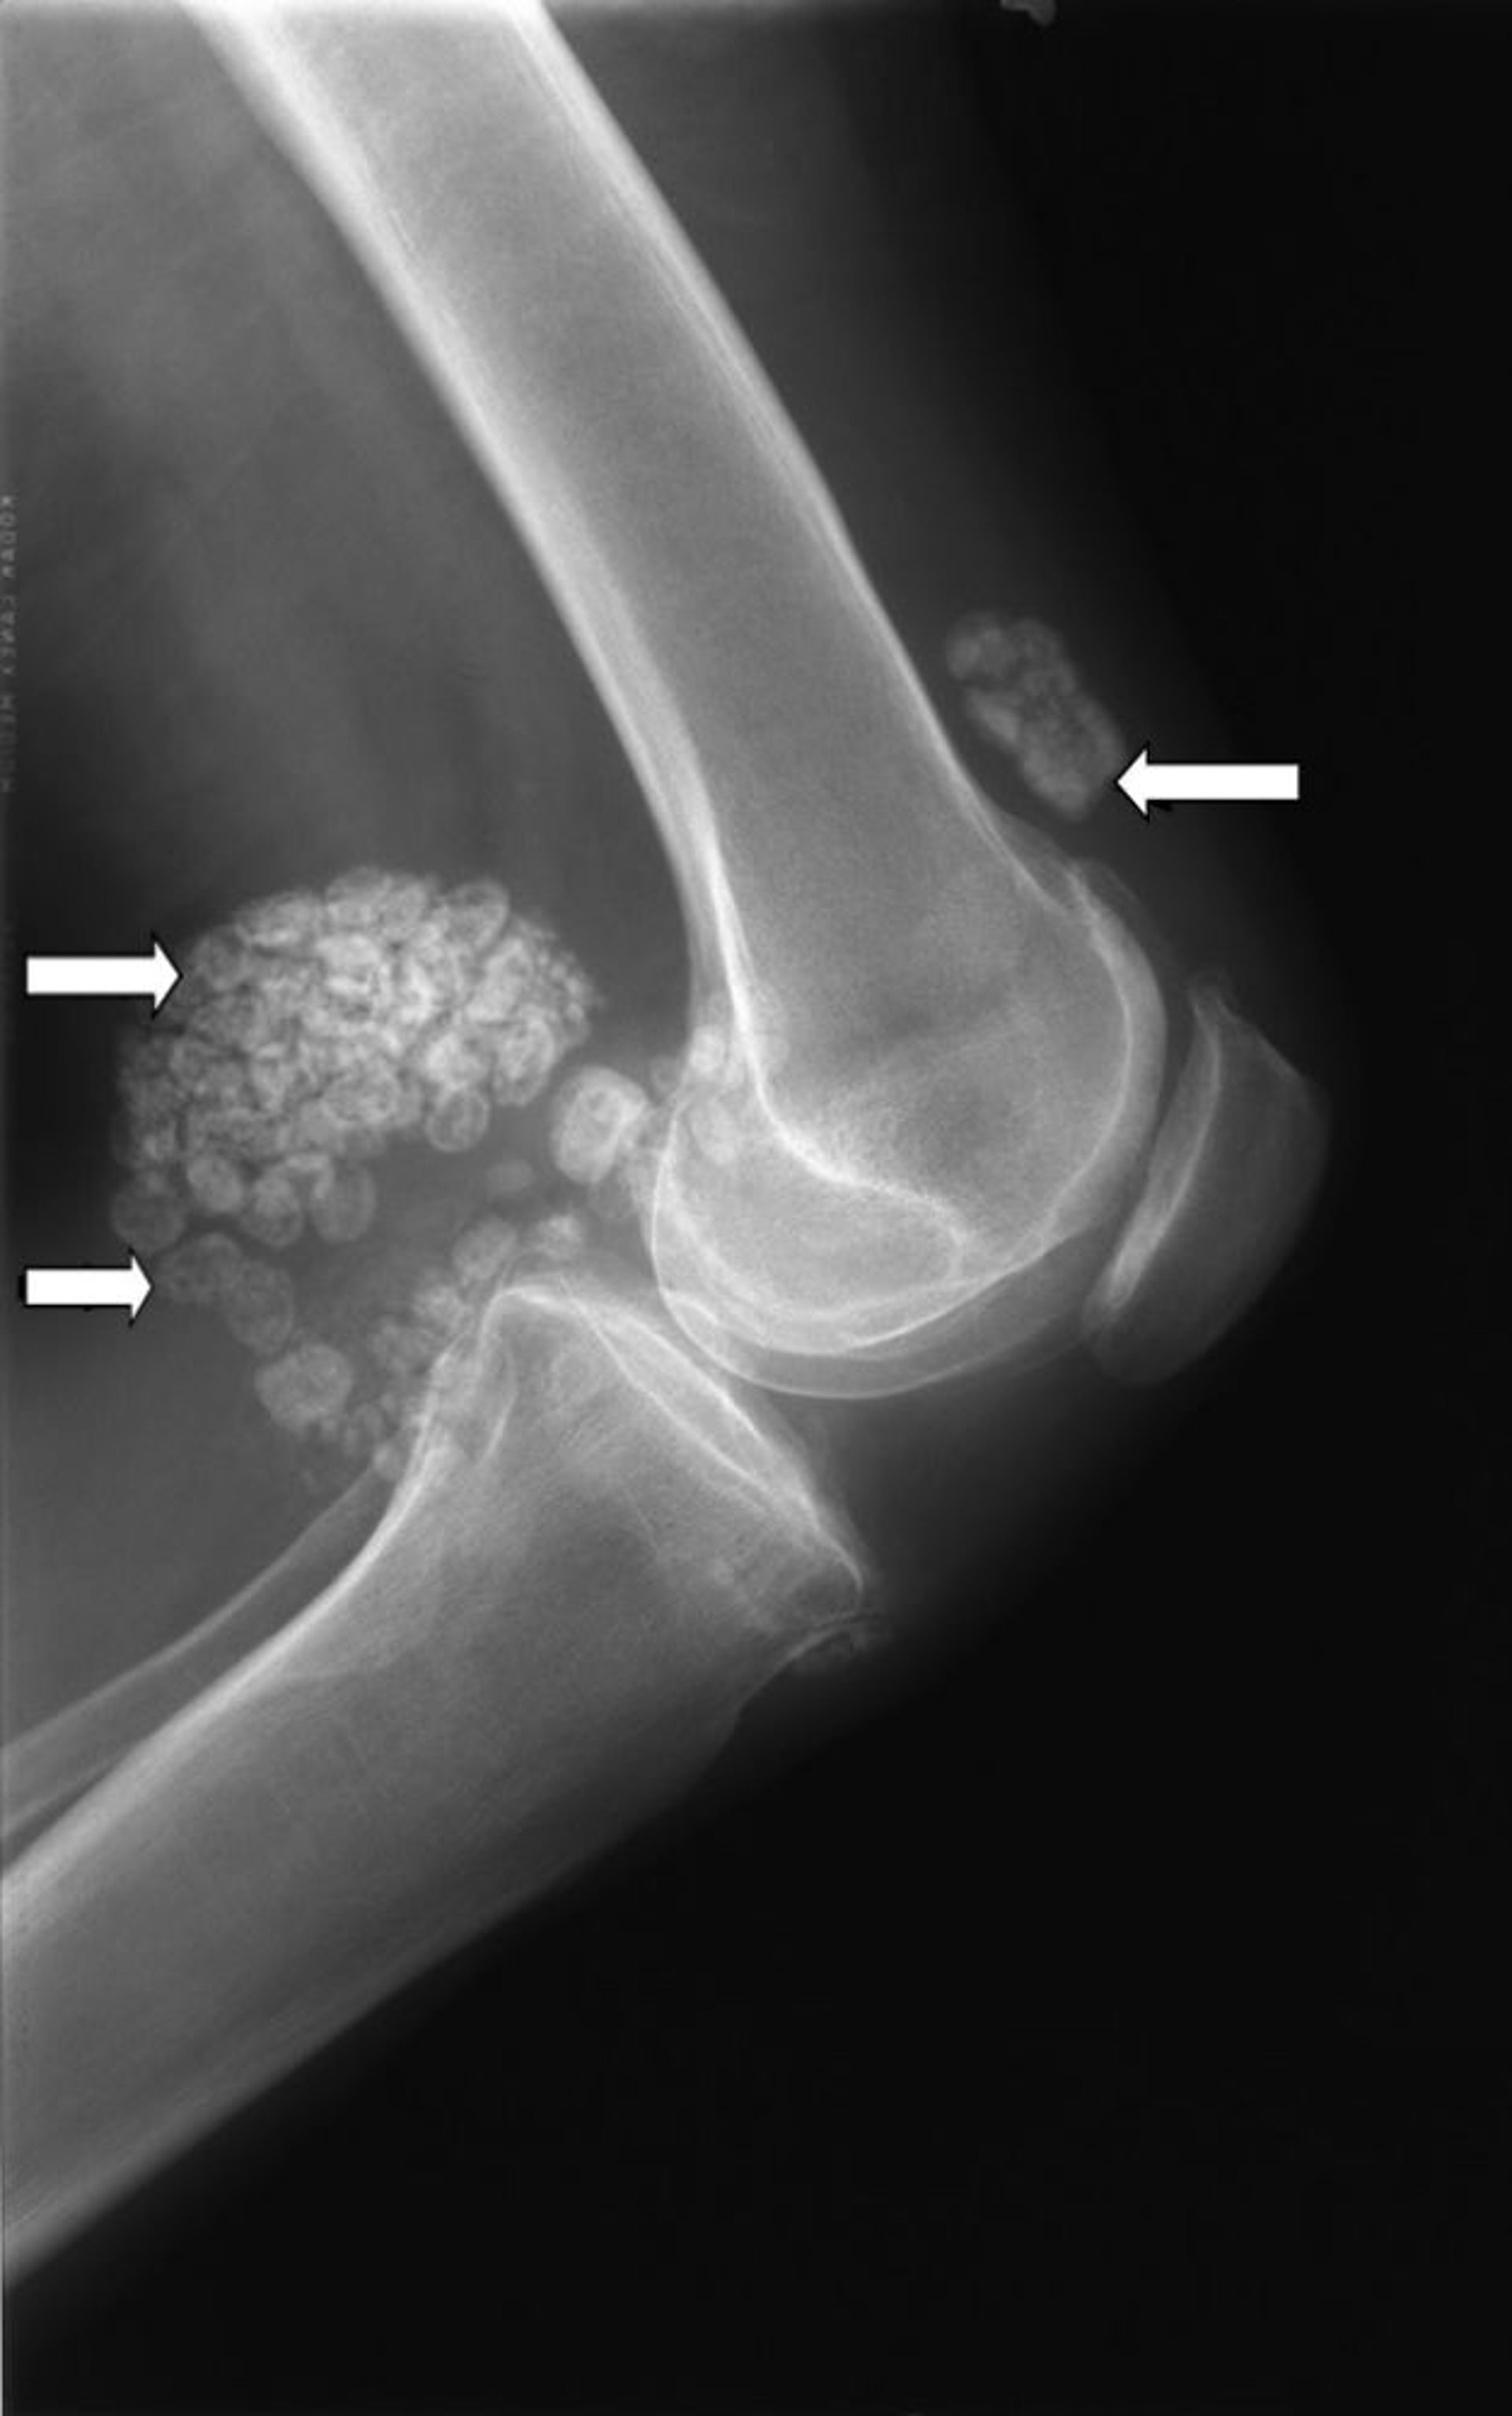

Esta radiografía de la rodilla muestra múltiples acumulaciones de cartílago (flechas) conocidas como condromatosis sinovial.

Imagen cortesía de Michael J. Joyce, MD, y Hakan Ilaslan, MD.